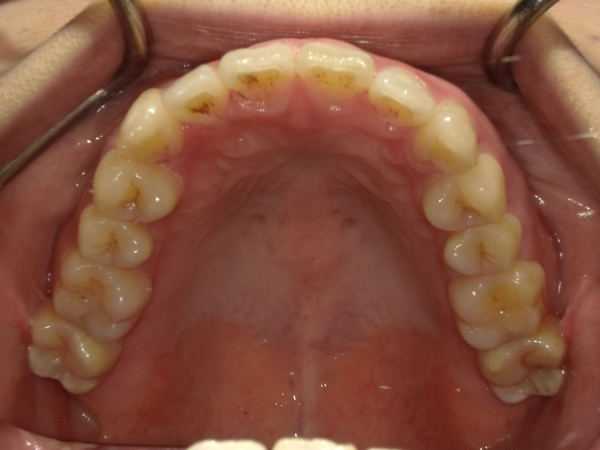

ガタガタとした歯並びや八重歯(叢生)CASE7